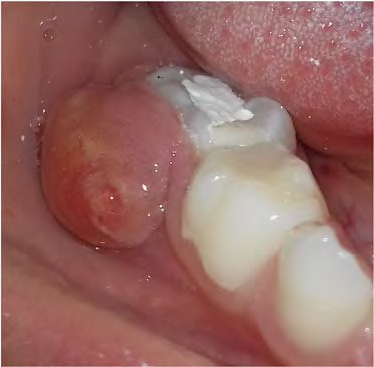

Figura D

Uma criança de 4 anos de idade, afebril e em bom estado geral compareceu para tratamento de urgência em função do surgimento de um nódulo de consistência amolecida e coloração amarelada, medindo 1 cm de diâmetro, localizado na região vestibular do dente 85. palpação do nódulo, houve a saída de secreção purulenta. A mãe informou que, há três meses, a criança havia passado por um atendimento de urgência, e na ocasião, havia sido colocada apenas uma “massinha no dente”.